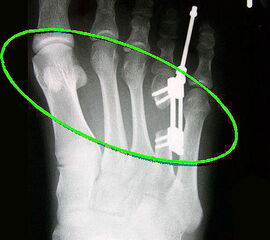

Das im Folgenden vorgestellte Operationsverfahren beschreibt die Kallusdistraktion von Metatarsalia nach den Prinzipien von Ilisarov 21 unter Verwendung eines internen, winkelstabilen Titan-Minifixateur (Klauser 2009). Der interne Distraktor ermöglicht während der Distraktions- und der Durchbauungsphase aufgrund seiner hohen Stabilität je nach Modell (18 mm, 23 mm) eine Verlängerung von bis zu 25 mm. Nach interner Anlage des Minifixateurs, meist lateral, kann über eine kontinuierliche Kallusdistraktion der Metatarsalebogen unter frühzeitiger Mobilisation im Gips oder Short-Walker rekonstruiert werden 15. Über einen interdigital und transcutan ausgeleiteten Aktivatorstab wird die Distraktion vom Patienten selber täglich morgens und abends durchgeführt. Zusätzlich vorliegende Strahlpathologien, wie zum Beispiel eine verkürzte Strecksehne oder ein kontraktes Metatarsophalangealgelenk können im Rahmen der Erstoperation ebenso therapiert werden wie z.B. ein Hallux valgus, ein Hallux valgus interphalangeus und/oder ein Digitus quintus varus (Klauser 2009). Nach Rekonstruktion des Metatarsalebogens wird in einem zweiten, kleinen Eingriff der Aktivatorstab über eine Spezialpinzette diskonnektiert und entfernt, wobei der Distraktor als interne Fixation belassen wird. Die Entfernung des Distraktors erfolgt in der Regel nach 9 – 12 Monaten, da es sich meist um angeborene kindliche Fehlbildungen handelt (Brachymetatarsie) und eine operative Intervention frühzeitig im Kindesalter erfolgen sollte (Klauser 2009).

• Spezial-Instrumentarium mit je einem Minifixateur (GENOS Mini 4x) 18 mm und 23 mm  sowie je 1x Linkskardanik / Rechtskardanik für die entsprechende Distraktionslänge sowie das dazugehörende, im Set befindliche Schrauben-Set mit 2,0 mm und 2,3 mm starken, winkelstabilen Schrauben mit Bohraufsteckhülse.

Meist kam ein 18mm Minifixateur zur Anwendung und ausnahmslos wurde er lateral am Metatarsale implantiert. Bis auf das Metatarsale 5 wurden vom Autor alle weiteren Metatarsalia (MT1 – MT4) isoliert oder kombiniert verlängert. In 7 Fällen wurde eine simultane Verlängerung zweier Metatarsalia (2x MT1 und MT4, 4x MT3 und MT4, 1x MT2 und MT3) vorgenommen. Bei einem Großteil der Patienten musste eine Strecksehnenverlängerung entweder im Rahmen der Erstoperation oder im Rahmen der Aktivatorentkopplung vorgenommen werden. In neun Fällen (ausnahmslos bei Erwachsenen > 30 Jahre) sogar 2x sowohl während des Erst- als auch Zweiteingriffes. Annähernd regelhaft sind bei den eben genannten Eingriffen Arthrolysen des Metatarsophalangealgelenks des betroffenen Zehenstrahls erforderlich, da durch die Distraktionsverlängerung eine hohe Kompression auf das jeweilige Grundgelenk entsteht.